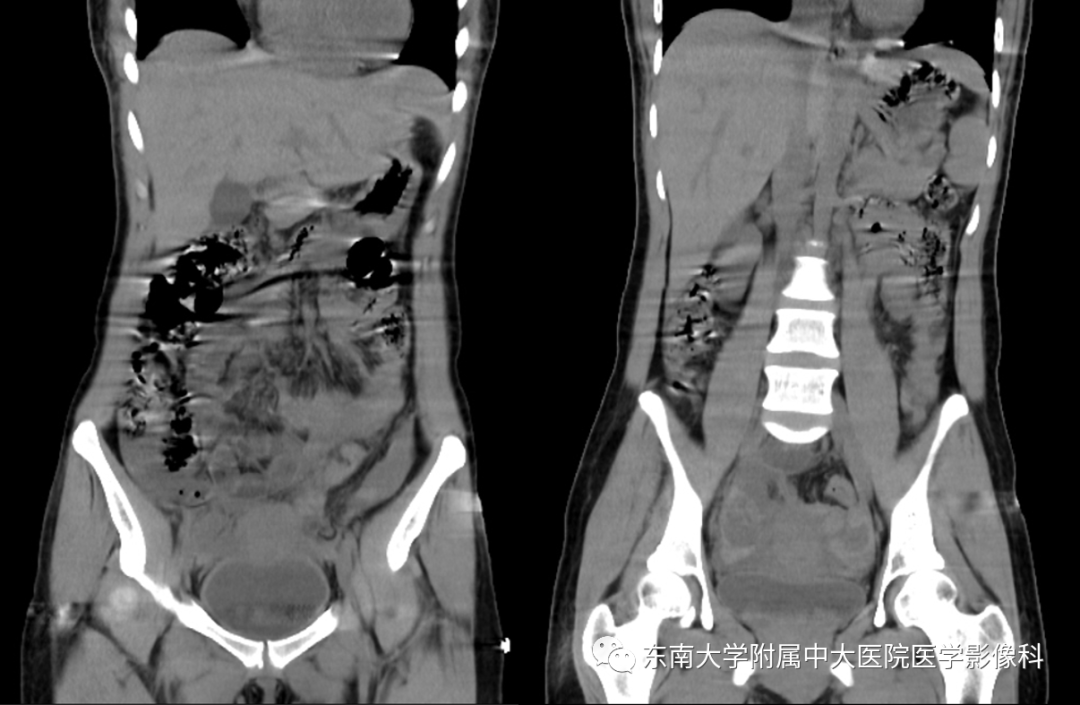

病史

女,24岁,因“停经42天,下腹痛3小时”入院

影像学表现

病例结果:宫外孕破裂